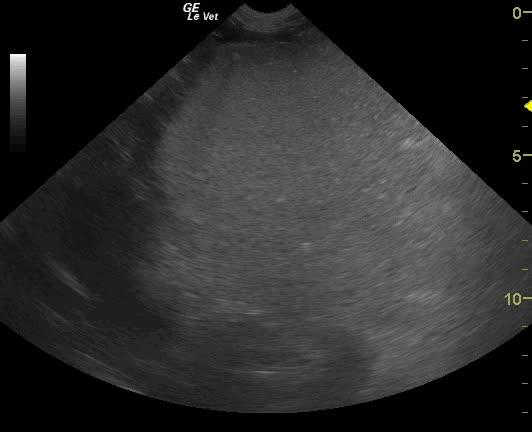

Severe gastric air artifact is noted when imaging the stomach. The normal pylorus is not visible from the right 11-13 intercostal approach suggestive for pyloric displacement. Splenic congestion and splenomegaly is present.